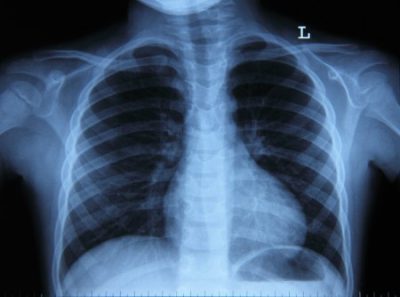

Флюорография предполагает определенные результаты, норма для которых, это – четкий рисунок дыхательных органов. В пределах одной и той же ткани не должно наблюдаться затемнений или светлых пятен. Именно такая расшифровка флюорографии считается нормальной.

Для пациентов важно, что может быть выявлено в ходе такого обследования. Следует сказать, что флюорография покажет очень многие проблемы – даже на начальном этапе их развития. В первую очередь на изображении видно, что пациент курящий.

Легкие курильщика обычно отличаются тяжистыми корнями. Именно это позволяет узнать, что перед врачом флюорография курильщика. Тревожиться на этот счет не нужно, хотя многие отказываются от такого обследования именно из-за того, что о вредной привычке узнает врач (якобы специалист станет упрекать из-за того, что куришь).

Доктор не занимается перевоспитанием больных, поэтому он просто констатирует факт вредного пристрастия, не более. Хотя курение является очень опасной привычкой для органов дыхания и организма в целом. Также указанная особенность может говорить о развитии бронхита.

При расширенных и уплотненных корнях можно предполагать такие заболевания, как бронхит или пневмонию. Усиленный сосудистый рисунок наблюдается при чрезмерном кровоснабжении. Данное явление может стать признаком воспалительного процесса или проблем с сердечно-сосудистой системой.

При наличии очаговых теней следует учитывать их расположение. Если они обнаружены в нижней или средней части легкого, то это признак пневмонии. Верхнее расположение таких теней позволяет предположить развитие туберкулеза.

Кроме этих, на снимке могут быть обнаружены и другие отклонения. Важно, чтобы заключение флюорографии делал врач, поскольку только он может правильно оценить выявленные особенности. Также следует учесть, что показанный на снимке результат иногда бывает ошибочным, если была нарушена техника выполнения.